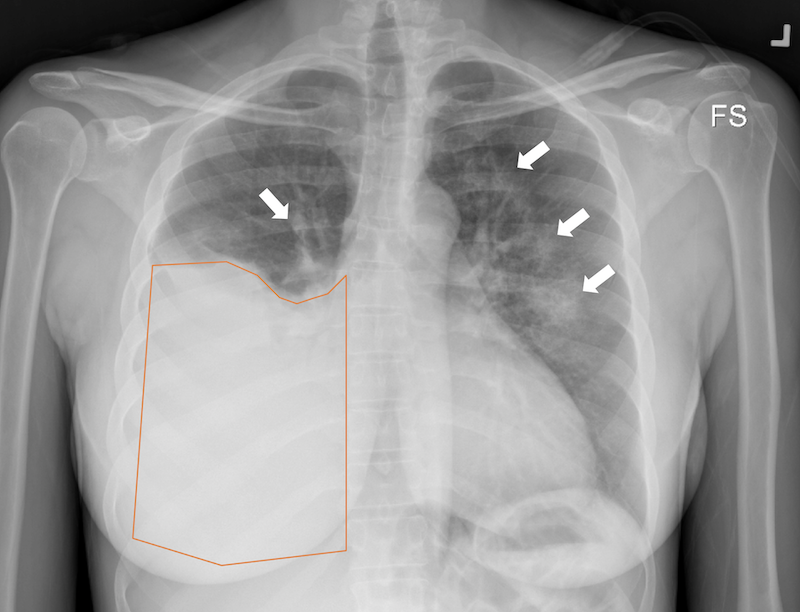

Présence d’air dans la cavité pleurale

Traumatisme de la paroi thoracique → augmentation V air emprisonné ds cavité pleurale → baisse V pulmonaire → affaissement partiel ou complet des poumons

Emprisonnement de l’air ds la cavité pleurale mais qui ne peut s’en échapper → élévation importante de la pression intrapleurale → poumon du côté atteint, coeur et gros vaisseaux se compriment → refoulement → baisse retour veineux → chute de tension importante → mort